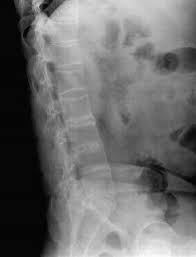

导读: 强直性脊柱炎是以侵犯骶髂关节及脊柱为主要特点的慢性炎性疾病,部分累及髋、膝关节。该病初期表现为下腰痛,逐渐由间断性转变为持续性,并出现僵硬,僵硬以晨起为著。

导读: 强直性脊柱炎的早期症状比较隐匿,强直性脊柱炎患者可出现厌食、低热、乏力、消瘦和贫血等全身症状,少数病例可有长期低热和关节痛,酷似风湿热表现,个别情况以高热、外周关节等急性炎症表现。强直性脊柱炎患者多为

导读: 如果初期的强直性脊柱炎没有得到及时治疗,或者没有采取正确的方法治疗,疾病就可能恶化,转变为中期。这个时期的强直性脊柱炎表现危害较初期严重,而且治疗难度也会增加。因此疾病要及早治疗才好。

导读: 一旦患有强直性脊柱炎,由于疾病起病较隐匿,所以导致多数患者在患病早期都不能及时的发现疾病,指导病情严重了,才发现自己的病情已经到了疾病的晚期,这时候强直性脊柱炎的症状也相当明显了。